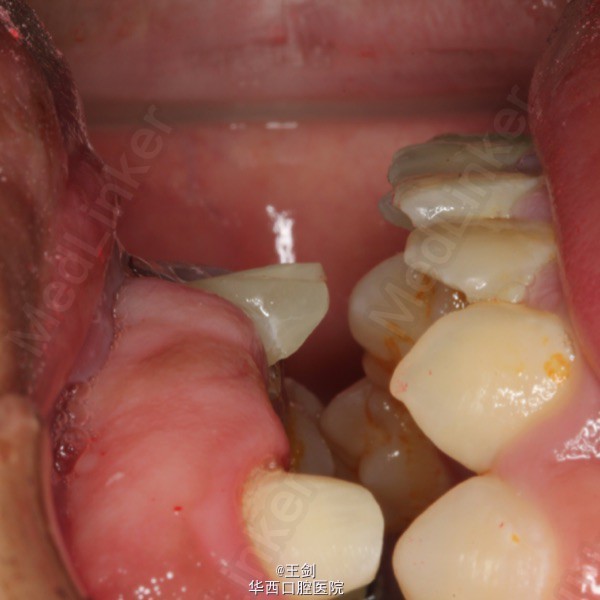

由于11牙正好位于中线,为保证修复效果,11牙作截冠处理,12牙残根纤维桩修复,并将12牙做成11牙的形态,最后做固定桥修复。图中显示牙体预备后正侧面观,可见前牙为反合状态,通过固定桥修复讲前牙关系改为切合。最后一图为戴暂冠后